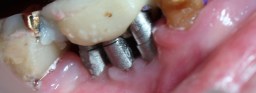

| 91才で44、45にインプラント 2012年03月06日撮影(92才) 術後約6ヶ月 非喫煙者 |

上記のインプラント部分を拡大 高齢で歯磨きが上手に出来ないので 歯垢(プラーク)が歯やインプラント部分に 付着。 |

| 同部分をきれいに磨いてやると 金属色のインプラントがきれいに見えます。 インプラント部分の歯ぐきに炎症なし。 |

| インプラント植立後4年10カ月後 高齢のため最終補綴を入れずにTEK(仮歯)のままです。 仮歯で状態がよければ2〜10年は持ちます。 壊れた時に最終補物を入れるか再度TEKを作ります。 2016年01月09日撮影(96才) どんなにプラークがついてもインプラント周囲炎は起こりません。 |